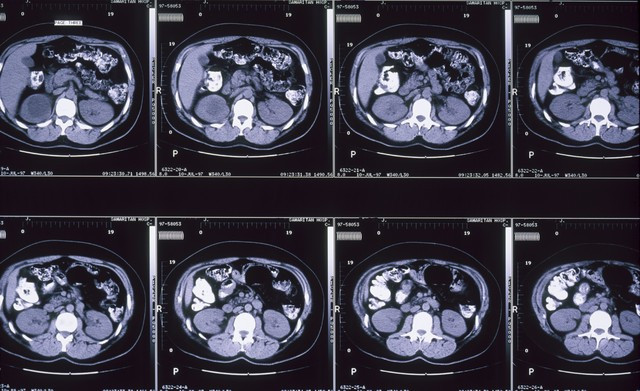

举例这位患者,男,56岁,肝囊肿2.3 cm×1.8 cm,肾囊肿3.1 cm×2.7 cm,泛泛腰酸腰痛,晚上要起夜四五四次,头晕耳鸣,眼睛看东西模模,干点活就心慌气短,浑身没力气,右边胁肋部偶尔会隐隐作痛,尤其是不悦大概累着之后,疼得更澄莹。

患者用药崇拜一段时辰后,再来复诊的期间,腰酸腰痛、晚上起夜、头晕耳鸣、看东西微辞、心慌气短、浑身没力气、右肋隐隐作痛的问题基本皆褪色的七七八八了。复查B超,肝囊肿减轻到1.5 cm×1.2 cm,肾囊肿减轻到2.1 cm×1.7 cm。